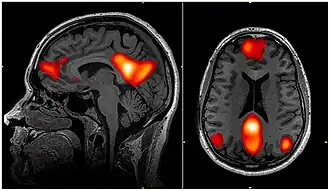

Dynamic functional connectivity (DFC) refers to the observed phenomenon that functional connectivity changes over a short time. Dynamic functional connectivity is a recent expansion on traditional functional connectivity analysis which typically assumes that functional networks are static in time. DFC is related to a variety of different neurological disorders, and has been suggested to be a more accurate representation of functional brain networks. The primary tool for analyzing DFC is fMRI, but DFC has also been observed with several other mediums. DFC is a recent development within the field of functional neuroimaging whose discovery was motivated by the observation of temporal variability in the rising field of steady state connectivity research.

Functional connectivity refers to the functionally integrated relationship between spatially separated brain regions. Unlike structural connectivity which looks for physical connections in the brain, functional connectivity is related to similar patterns of activation in different brain regions regardless of the apparent physical connectedness of the regions.[1] This type of connectivity was discovered in the mid-1990s and has been seen primarily using fMRI and Positron emission tomography.[2] Functional connectivity is usually measured during resting state fMRI and is typically analyzed in terms of correlation, coherence, and spatial grouping based on temporal similarities.[3] These methods have been used to show that functional connectivity is related to behavior in a variety of different tasks, and that it has a neural basis. These methods assume the functional connections in the brain remain constant in a short time over a task or period of data collection.

In addition to complaints that DFC may be a product of scanner noise, observed DFC could be criticized based on the indirect nature of fMRI which is used to observe it. fMRI data is collected by quickly acquiring a sequence of MRI images in time using echo planar imaging. The contrast in these images is heavily influenced by the ratio of oxygenated and deoxygenated blood. Since active neurons require more energy than resting neurons, changes in this contrast is traditionally interpreted an indirect measure of neural activity. Because of its indirect nature, fMRI data in DFC studies could be criticized as potentially being a reflection of non neural information. This concern has been alleviated recently by the observed correlation between fMRI DFC and simultaneously acquired electrophysiology data.[24] Battaglia and colleagues have tried to address those controversies, linking dynamic functional connectivity to causality or effective connectivity. The scientists claim indeed that dynamic effective connectivity can emerge from transitions in the collective organization of coherent neural activity. [25]

fMRI is the primary means of investigating DFC. This presents unique challenges because fMRI has fairly low temporal resolution, typically 0.5 Hz, and is only an indirect measure of neural activity. The indirect nature of fMRI analysis suggests that validation is needed to show that findings from fMRI are actually relevant and reflective of neural activity.